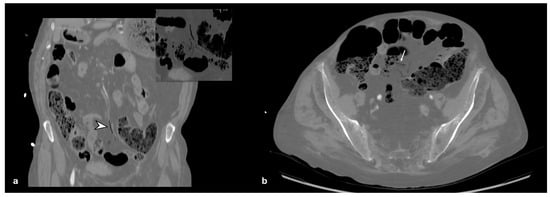

2. Case Report